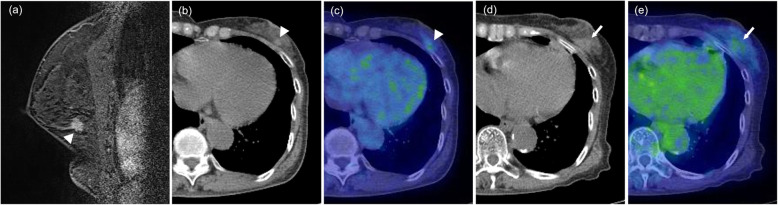

Fig. 4.

Non-fatty mass. A 73-year-old woman with invasive ductal carcinoma. Breast MRI before cryoablation (a, arrowhead) showing an irregularly shaped nodule of diameter 11 mm in the outer-lower quadrant of the left breast. The pre-cryoablation CT portion (b, arrowhead) and fusion image (c, arrowhead) of PET/CT show a solid nodule with abnormal FDG uptake (SUVmax, 1.78). The CT portion (d, arrow) and (e, arrow) fusion image of PET/CT that was obtained 11 months after cryoablation shows a non-fatty mass and subtle FDG uptake in the treated area (SUVmax, 1.86)